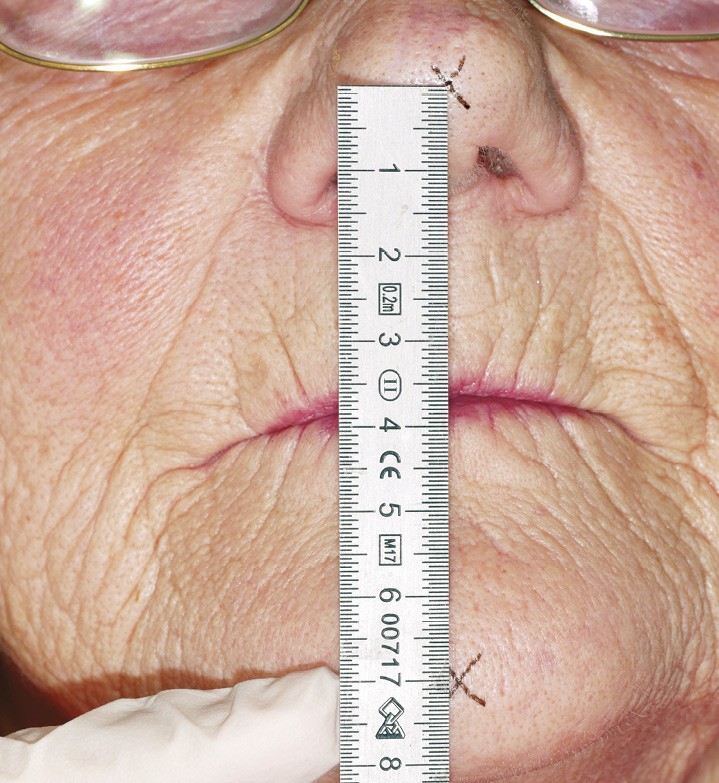

Les techniques indirectes font appel à la DVR comme variable intermédiaire. Des croix sont tracées au crayon dermographique sur deux points tégumentaires non mobilisables par la mimique (relief antérieur du menton et partie basse de l’arête du nez) (fig. 18). Une fois le patient placé en position de repos, le praticien mesure la distance entre les deux croix tracées à l’aide d’une réglette métallique ou d’un compas à pointe sèche (fig. 19).